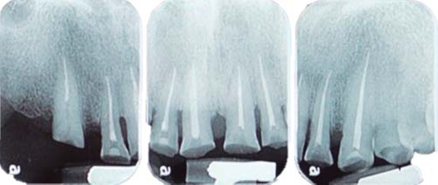

Este reporte documenta el tratamiento de un paciente masculino de 68 años de edad. Comenta tener dificultades masticatorias y digestivas debido a importante desgaste dental, se dice incómodo al sonreír; no refirió padecimientos sistémicos, fumó durante ocho años, diagnosticado con hipertensión arterial controlada. Se observa atrición generalizada, ausencia de dientes 14, 15, 16, 46 y periodonto sano (Figuras 1a4). Los dientes 13 y 37 presentaban tratamiento de conductos y periápice sano, sin restauración (Figura 5).

Para cuantificar la reducción de DVO, se examinó el perfil facial y la estética mediante análisis fotográfico y vídeo (Figuras 6y7). Además de realizar un cuidadoso análisis del montaje de los modelos diagnósticos en articulador semiajustable (Figura 8). También se examinó el esquema oclusal (presentaba relación borde a borde) y la estructura dental con la que se contaba (Figura 3). La revisión dinámica fue clave para determinar que el paciente exhibe una línea de sonrisa alta (Figura 9).

Mediante evaluación radiográfica de la relación corona-raíz, se realizó el alargamiento de la corona en el sextante anterosuperior para exponer suficiente estructura dental y lograr una retención adecuada para las restauraciones finales (Figuras 16a22).

Un nuevo plano oclusal se estableció preparando el arco superior e inferior para coronas completas (Figura 24).